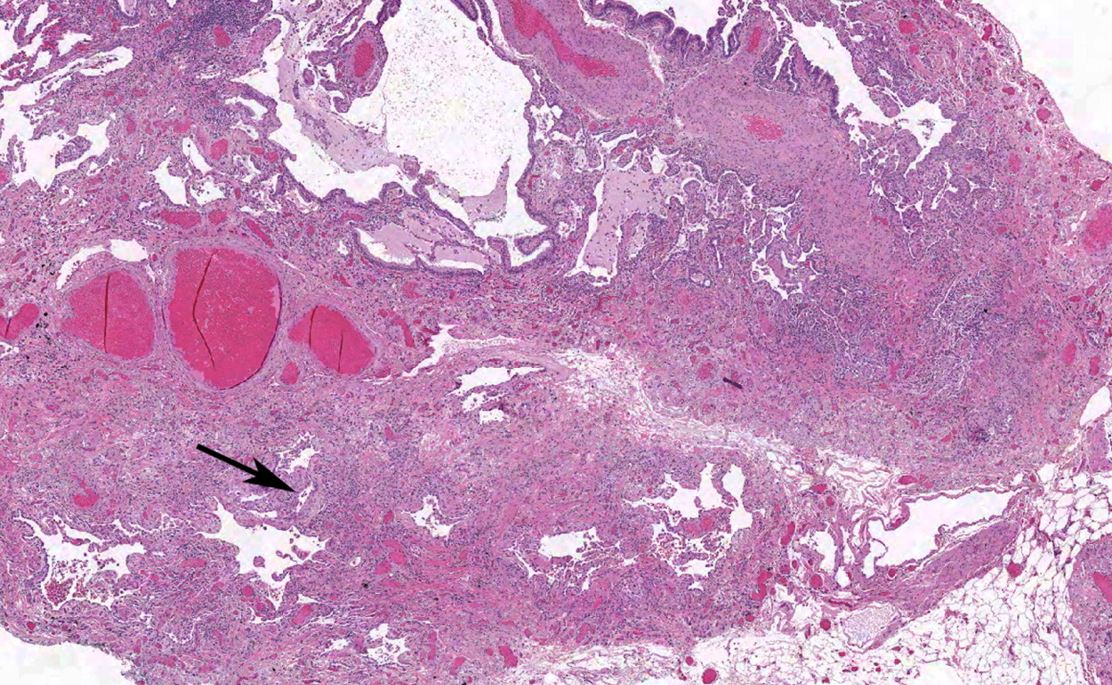

HISTOPATHOLOGY: UIP PATTERN5,6,18

- Dense fibrosis with architectural distortion (i.e., destructive scarring and/or honeycombing)

- Predominant subpleural and/or paraseptal distribution of fibrosis

- Patchy involvement of lung parenchyma by fibrosis

- Fibroblast foci

Absence of features to suggest an alternate diagnosis

Image used with permission from the American Thoracic Society.

© 2018. Raghu G et al.5